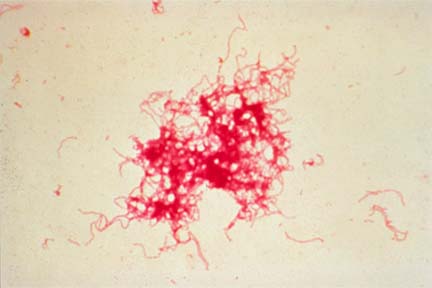

#betegség#egészség#fájdalom#fekélyElkerülhető a fájdalom megjelenése, a stressz elkerülésével?@sittpljsz•2023. máj. 17.•1 perc olvasás